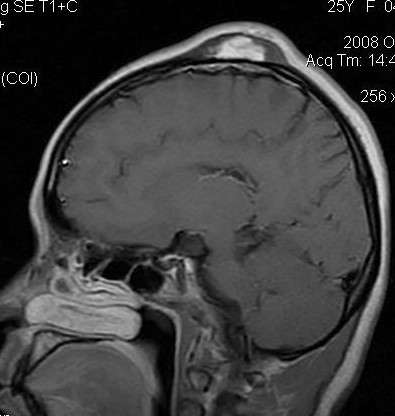

mri表现为头皮下肿块,t1wi为等信号,t2wi为高信号.并清晰显示

头颅mri入门系列之认识序列3